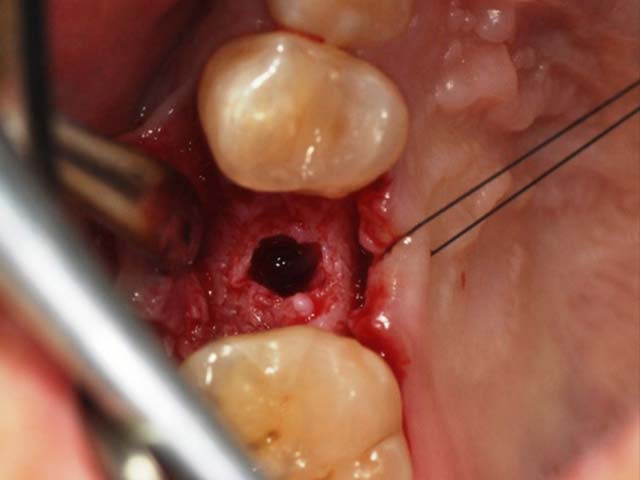

齒槽骨保存術+植牙 首頁 案例分享 人工植牙 齒槽骨保存術+植牙 STEP1拔除掉無法使用的斷裂牙根 STEP2齒槽骨保存術—使用骨粉填補拔牙傷口 術前 V.S 術後 植牙第一階段—植入牙根 植牙第二階段—製作正式假牙